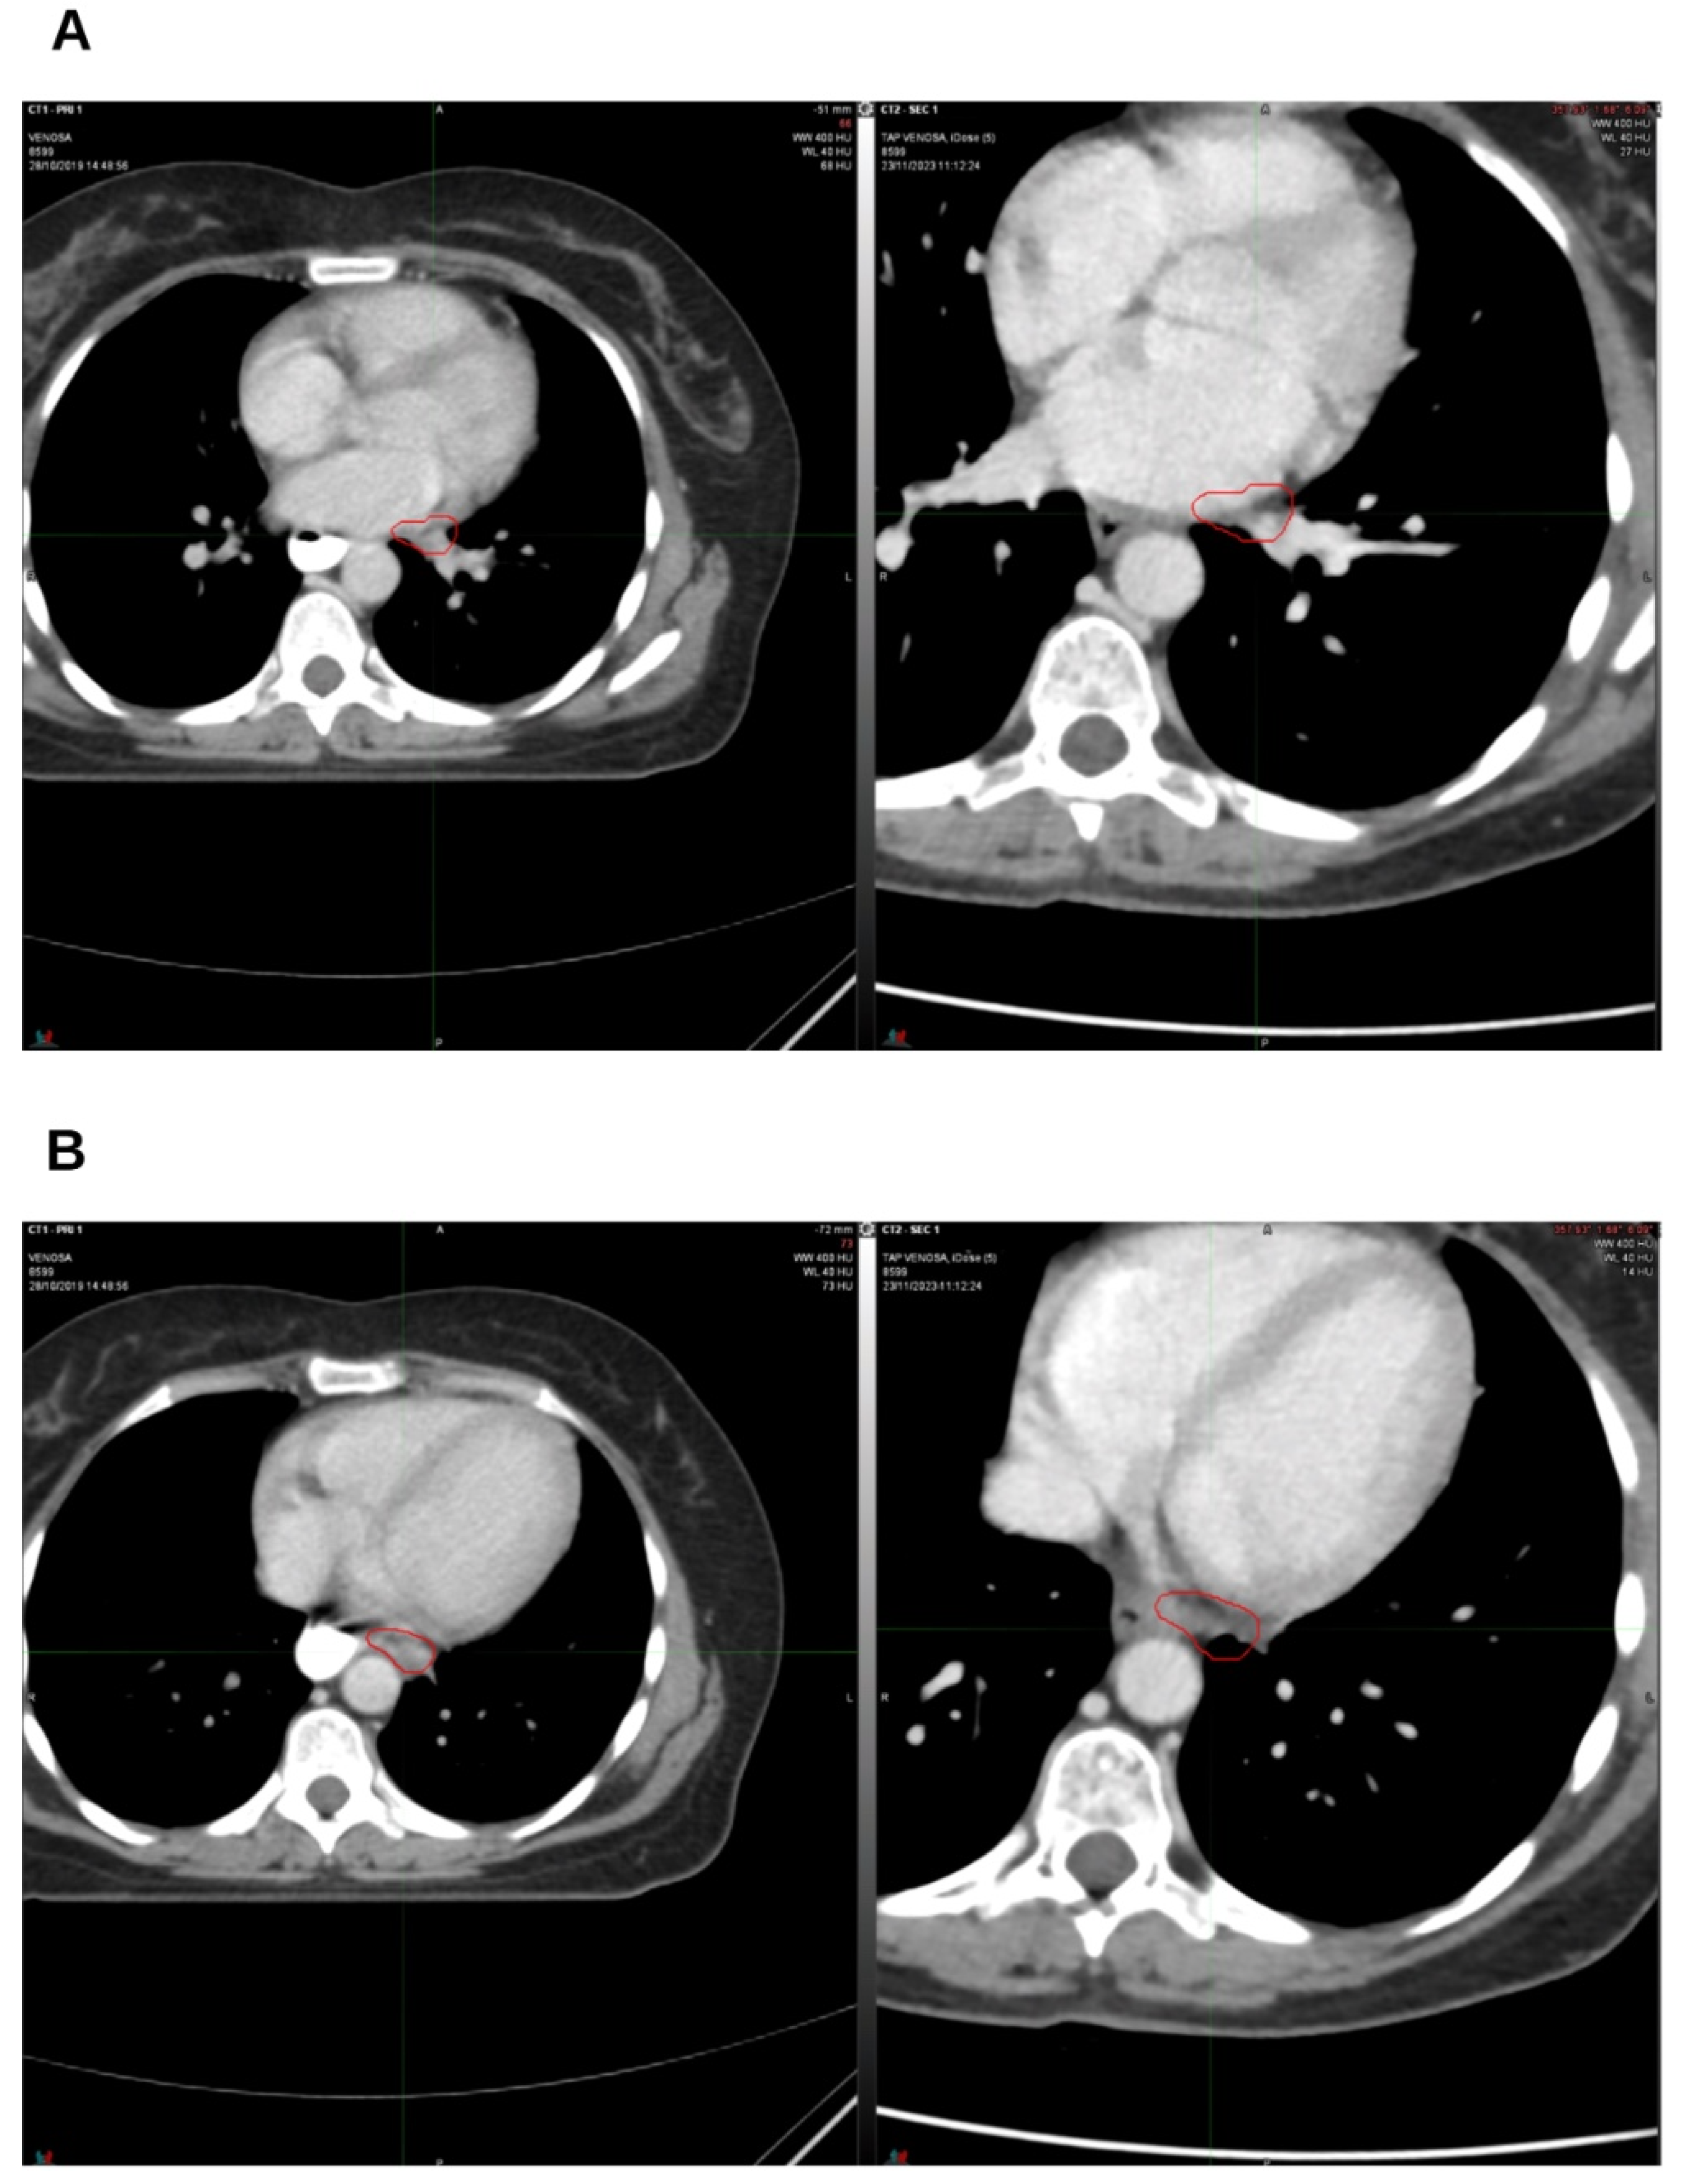

2. Case Presentation